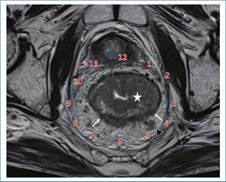

Por otro lado, no solo debemos describir la ubicación topográfica de las lesiones, sino también describir su patrón de crecimiento (endofítico y/o exofítico), si generan compromiso completo o no de la circunferencia rectal o si generan estenosis de su luz. En este aspecto, nos es útil ubicar las lesiones en el plano circunferencial siguiendo el eje de las agujas del reloj (Fig. 7).

Estadificación N

El estadio N está determinado por la cantidad de nódulos linfáticos regionales comprometidos, considerándose: N1 el compromiso de uno a tres nódulos y N2 el de cuatro o más. En la tabla 3 se observan los criterios de sospecha de malignidad de los nódulos linfáticos1),(2),(3. Los nódulos linfáticos regionales son aquellos que se ubican a nivel de la FMR (incluyen presacros, mesentéricos inferiores y mesentéricos sigmoides), ilíaco interno y obturadores2,3. Por su parte, son considerados nódulos no regionales los ilíacos externos, ilíacos comunes e inguinales (M1) (Fig. 16). No obstante, los inguinales son considerados regionales en los casos de compromiso distal del canal anal (Fig. 17)3.